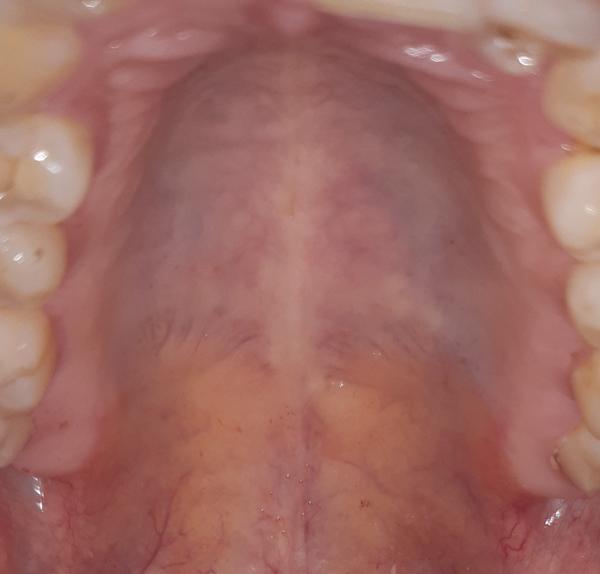

na fotografii vpravo, na tvrdém patře jsou viditelné jakoby 3 bledé "bouličky" neboli "výrůstky, výstupky". Všimla jsem si toho náhodou jazykem, jsou tvrdé, přijde mi to jako kost toho patra, ale na druhé straně nic takového nemám.

Je možné, že je to kost nebo výrůstky patra?

na fotografii je to velmi špatně hodnotitelné, nevidím tam žádnou abnormalitu. Doporučila bych vyšetření u PLDD, aby nález zhodnotil ev. doporučil další vyšetření (zubní nebo ORL).